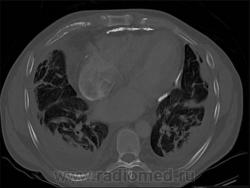

Иллюстрация 9.

Иллюстрация 10.

Иллюстрация 11.

35 - фиброзирующий альвеолит --> сотовое лёгкое